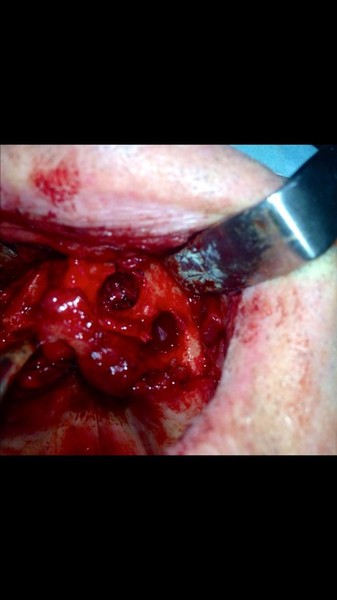

Implantologia avanzata con contestuale rimozione impianti e cisti

Video di una Parte dell'intervento in cui si puo' vedere la comunicazione tra impianti rimossi e pavimento nasale.